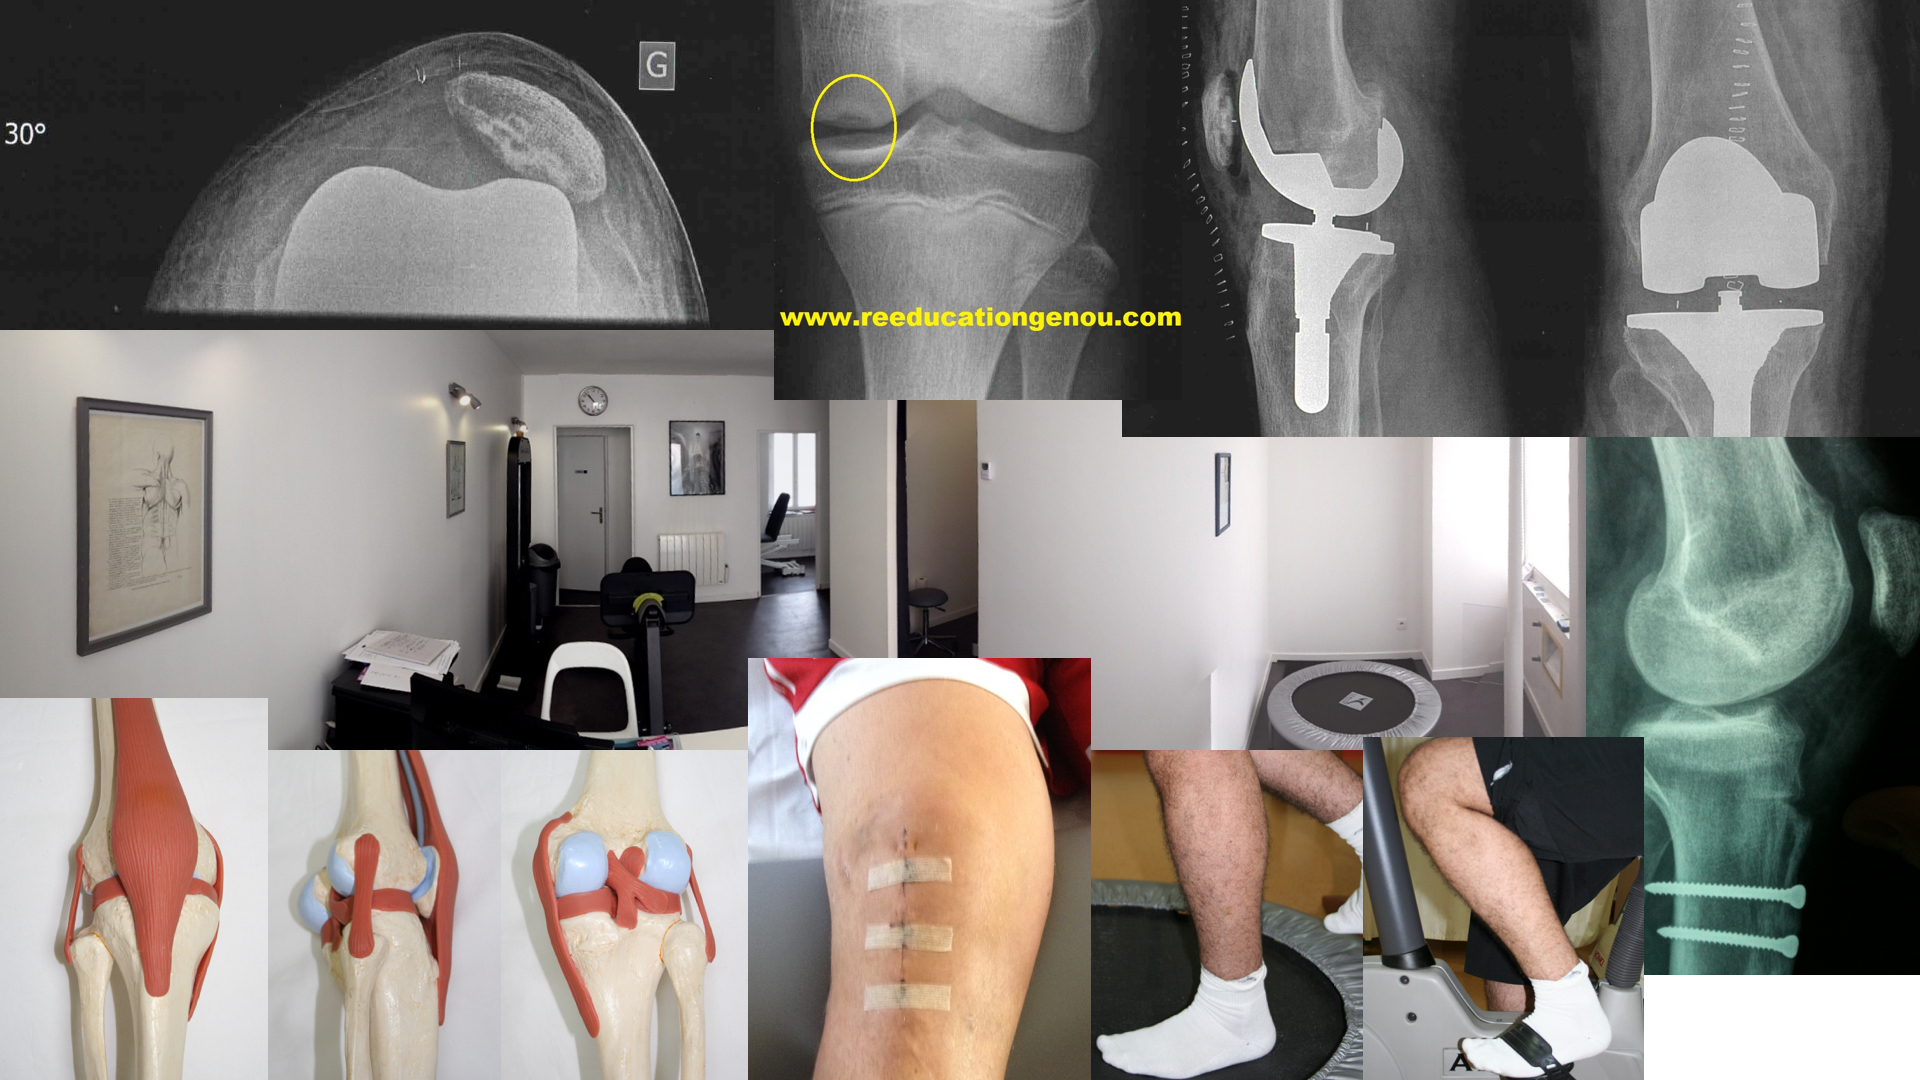

Du 15è au 21è jours post-opératoire à 3 mois environ

la cicatrice est fermée, les fils enlevés, le genou dégonfle doucement et les amplitudes sont au delà des 80 à 90° sans forcer

toutes les ligamentoplasties sont en rééducation les KJ comme les Didt !

DiDt sur presse, travail à 2 jambes (photo de 2006, cabinet des Maussins, 75019)